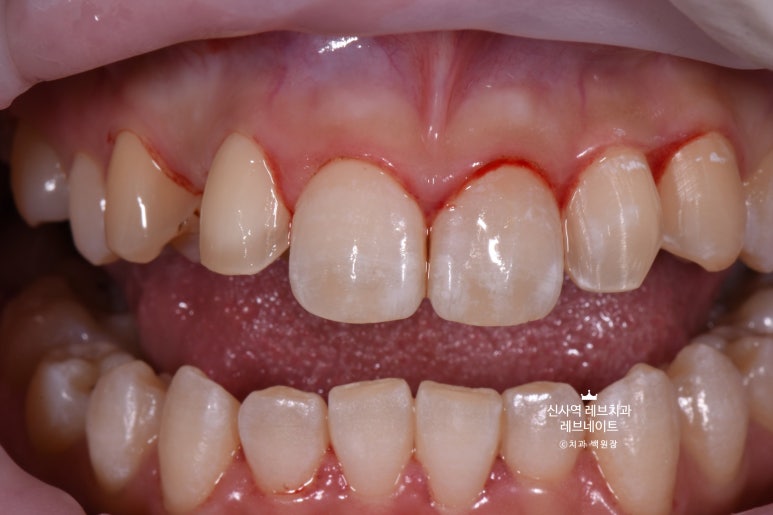

그냥 얼핏 보기엔 뭐.. 치열이 조금 틀어져 있네? 이 정도라고 생각이 드실텐데요

(저 또한 그랬습니다.)

이게 왠걸 ! 고개를 돌려보니 치아가 하나 없는겁니다...

어딨지? 하고 보니,

오른쪽 송곳니가 보다 안쪽에 있는 부정교합이라, 마치 치아하나가 없는 것 처럼 보이는 상태셨어요.

정면만 딱 보면 안보이는 것 같은데, 얘기하거나 웃을 때 엄청 잘 보이는 앞니 사이 공간이 있는거에요..

그리고 잘 보면, 치아들이 조금 뻐드러져 있기도 하고.. 뭔가 돌아가 있기도 하고..

시작하기 전에 깨끗이 스케일링을 해드렸습니다.

그리고 치아 색상을 측정해 둡니다.

다시 한 번 자세히 보면, 치아 색이 꽤 얼룩덜룩해보이는 것을 아실 수 있을거에요.